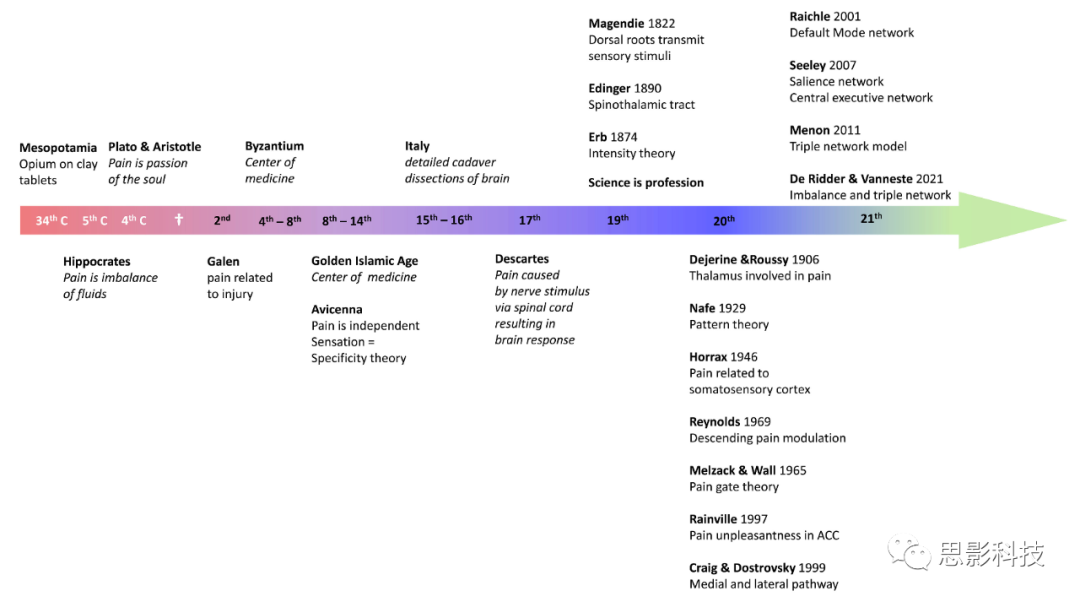

自有记录以来,疼痛一直由阿片类药物治疗。实际上,追溯到公元前3000年的美索不达米亚地区,用楔形文字写成的苏美尔粘土板上就已经提到了鸦片(13)。公元前800年,荷马在《奥德赛》中写道,宙斯的女儿海伦给了特勒马科斯阿片类药物,以减轻奥德修斯缺席带来的悲伤(13)。柏拉图和他的学生亚里士多德认为疼痛是一种情感,是灵魂的激情(14)。

希波克拉底,西方医学之父,生活在公元前460年至377年的希腊,也就是柏拉图和伯里克利的同时代人,是第一位认为疾病是自然引起的,而不是因为迷信和神灵的医生(15)。因此,他将医学与宗教分开:疾病不是神灵施加的惩罚,而是环境因素、饮食和生活习惯的结果(15)。他的作品被编入了《希波克拉底全集》,该集包含60本书。希波克拉底认为疼痛是体液失衡的结果。后来,在公元2世纪,伽林(Galen)指出疼痛总是组织损伤的结果(16)。这一观点可能源于他成为角斗士以及皇帝马库斯·奥勒留的医生的事实。伽林的大量作品将在接下来的近1400年内主导西方医学。

从8世纪到14世纪的伊斯兰黄金时代,医学的中心转移到了近东、北非和西班牙。阿维森纳(Avicenna,980–1,037)是第一个将疼痛描述为一种独立和特定感觉的人,从而产生了特异性理论(14, 16)。作为17世纪科学革命的代表人物,笛卡尔(Descartes)为疼痛提供了一种完全机械性的解释,与当前对疼痛病理生理学的认识没有太大不同。在1664年,他描述了一个上行的疼痛通路,其中外周刺激通过外周神经传输到脊髓,然后从那里传递到大脑中的松果体,最终达到意识(17)。

19世纪见证了科学作为一种职业的诞生,术语“科学家”在1833年由多才多艺的威廉·惠威尔(William Whewell,1794–1866)首次提出,取代了旧词“自然哲学家”(18)。第一份定期刊物可以追溯到1665年,当时法国的《Journal des sçavans》和英国的《Royal Society Philosophical Transactions》开始系统地发布研究结果。这种专业化创造了大量新的发现。1822年,马珍迪(Magendie)发现是背侧神经根,而不是腹侧神经根,传输感觉刺激,1890年,埃廷格(Edinger)描述了脊髓丘脑束(14)。1874年,厄布(Erb)建议可能需要用强度理论来取代追溯到阿维森纳但由穆勒(Muller)在1840年进一步发展的特异性理论,在这个理论中,强烈的刺激会激活通常处理其他感觉的感觉神经,使其变得疼痛(14)。20世纪初,德热林(Dejerine)和鲁西(Roussy)提出丘脑参与疼痛(14),1946年,霍拉克斯(Horrax)以高强度刺激体感皮层,产生疼痛(19)。1969年,雷诺兹(Reynolds)证明通过激活一个下行通路,中脑导水管周围灰质(periaqueductal gray)会调节疼痛(20),这触发了一年后梅尔扎克(Melzack)和沃尔(Wall)提出疼痛门控理论(21)。又过了30年,1997年,雷恩维尔(Rainville)使用PET扫描证明,疼痛的情感成分是由脑前扣带皮层(rostral anterior cingulate cortex)处理的(22),紧接着,在1999年,克雷格(Craig)和多斯特罗夫斯基(Dostrovsky)通过详细描述中央和侧向通路,统一了疼痛模型(23, 24)。

在2021年,De Ridder和Vanneste提出,疼痛是中央加侧向通路与下行通路之间的失衡(25, 26)(参见图1以获取概览)。这一理论进一步完善了我们对疼痛机制的理解,特别是在中央和侧向通路与下行通路之间的相互作用和平衡方面。这为未来疼痛治疗的研究和应用提供了新的视角。

图 1 | 疼痛研究历史概览。